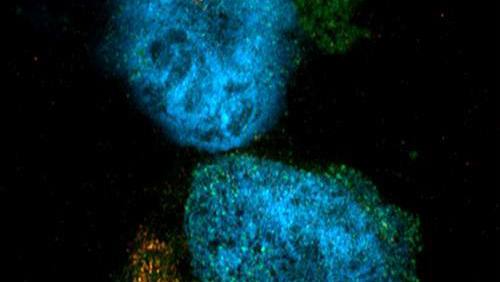

The inquisitive approach to problem-solving paid off. Dr. Gicobi, who recently completed her Ph.D. thesis, Dr. Dong and a team of Mayo Clinic researchers have provided a new understanding of the body’s cancer-fighting T cells, known as CD8+ T cells. In Science Advances, the research team describes a previously unknown type of CD8+ T cells that can withstand the toxicity of treatments like chemotherapy and radiation therapy. The cells, which they call resilient T cells, remain functional, suggesting there may be additional opportunity after chemotherapy and radiotherapy to target the cancer via the immune system. What’s more, the team identified a potential strategy to bolster the cancer-killing capabilities of these hardy cells.

As the team members looked further, they found the cells had heightened expression of the enzyme called malic enzyme 1, or ME1. “That was really interesting to us because ME1 is known to deal with molecules called reactive oxygen species, a metabolic byproduct that is important for the functions of immune cells but toxic when in excess. So we were looking at an enzyme that helps reduce the negative effects of metabolic pathways,” she says. The finding helped confirm that the resilient T cells in people are a distinct subgroup of CD8+ T cells.

She engineered the resilient T cells to overproduce ME1. The laboratory experiments found the increase of ME1 revived the cells and made them even better at killing off tumor cells. Importantly, Dr. Gicobi says, “We were able to increase their cancer-killing capacity without the accumulation of reactive oxygen species that induce cellular exhaustion.”